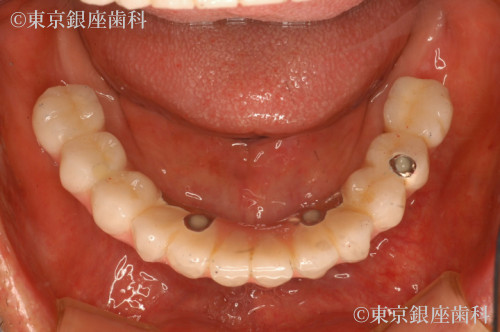

重度歯周病、義歯不適合による咬合障害をワンデイインプラントで改善した症例

After

全体的に歯周病が進行していること、咬合改善を希望されていることから残存歯を全て抜歯してワンデイインプラントにすることにした。